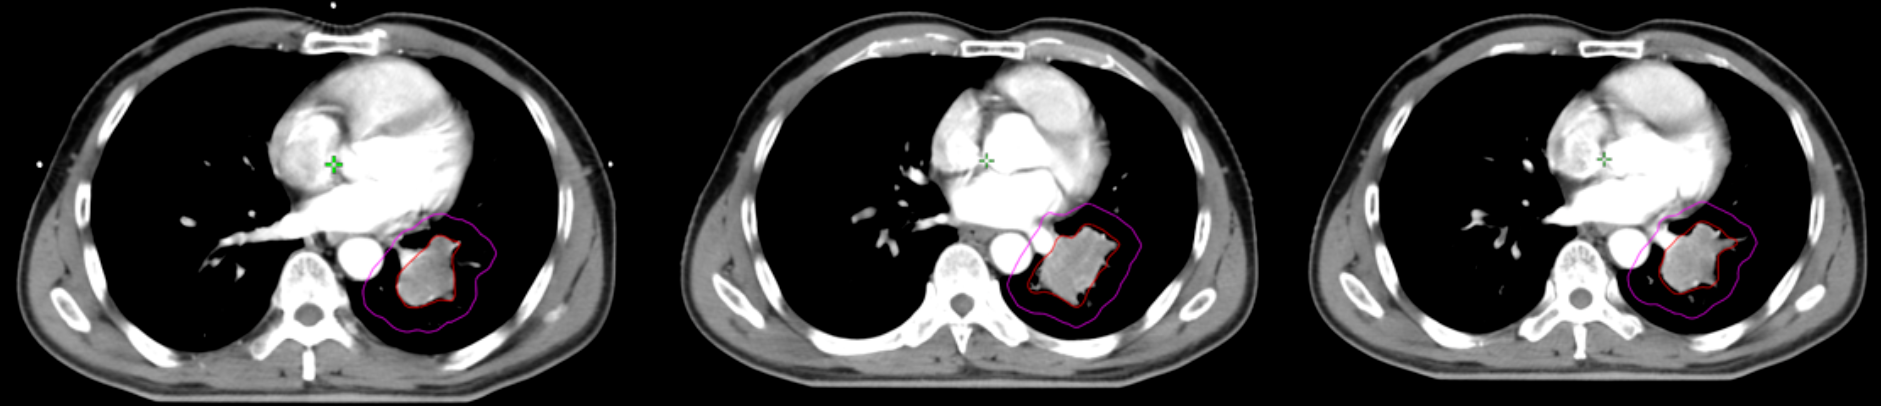

患者,60岁男性,确诊左肺期鳞癌(III期)。在接受化疗后,2025年9月复查显示左肺门肿块较前明显增大,并出现咳嗽、痰中带血的症状,疾病出现局部进展。为控制肿瘤、缓解症状,邵东市人民医院放疗团队为其制定了精准的放射治疗计划。

下图CT影像中,红色线条范围代表需要高剂量照射的核心肿瘤靶区,紫色区域则为保证治疗效果而扩大的安全边界,确保了放疗的精准性和安全性。

(▲患者放疗照射部位影像(部分)(放疗前))